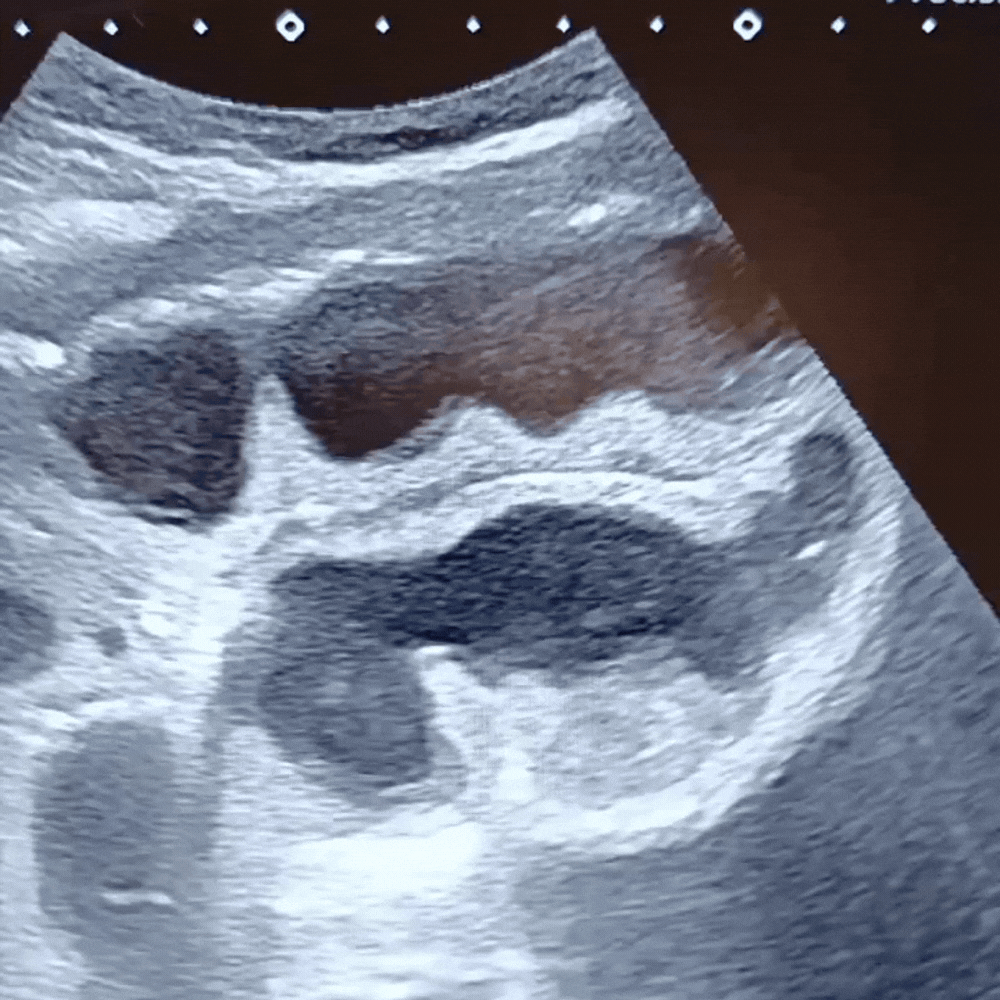

- Dilatation des anses grêles : diamètre > 25 mm (> 2,5 cm), contenu liquidien, paroi fine.

- Anses coliques : plus périphériques, contenu gazeux, haustrations visibles.

- Péristaltisme exagéré ou absent selon le stade (hyper puis paralytique).